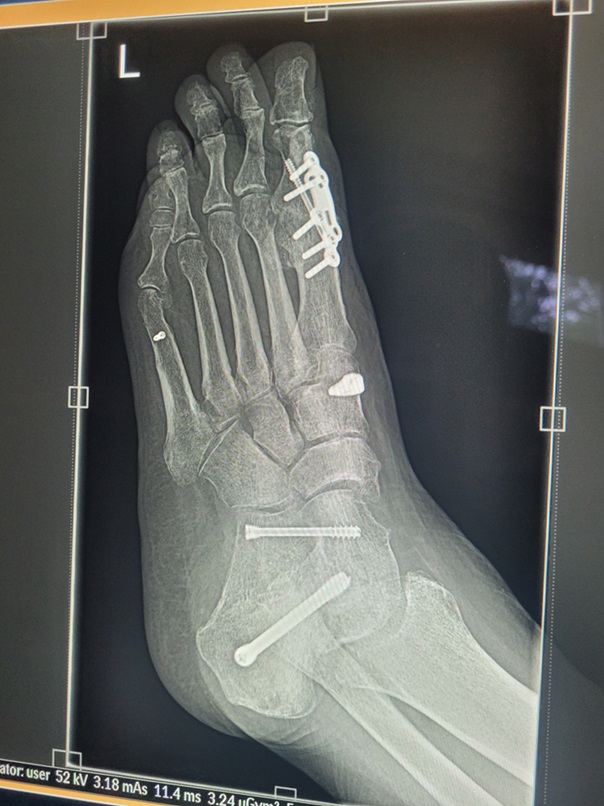

This issue will not apply to all surgeries either. It depends how long your post-op period is AND the degree of immobility required. For example, I’ve had both ankles fused. Same post-op period in both cases. However, with the left ankle I could drive four weeks earlier than with the right ankle and that four weeks, plus an additional, unrelated, hospitalisation, were enough to make what was, in my case, a major difference.

When I had the left ankle done in 2023, by the time I was in a moonboot and on crutches I could drive to the gym and do the weighted back exercises I needed to do to maintain my posterior chain strength. With the right ankle, obviously I couldn’t drive for an additional month. Then, two weeks after I could drive, I was back in hospital for a nasal/sinus infection. Essentially immobile again.